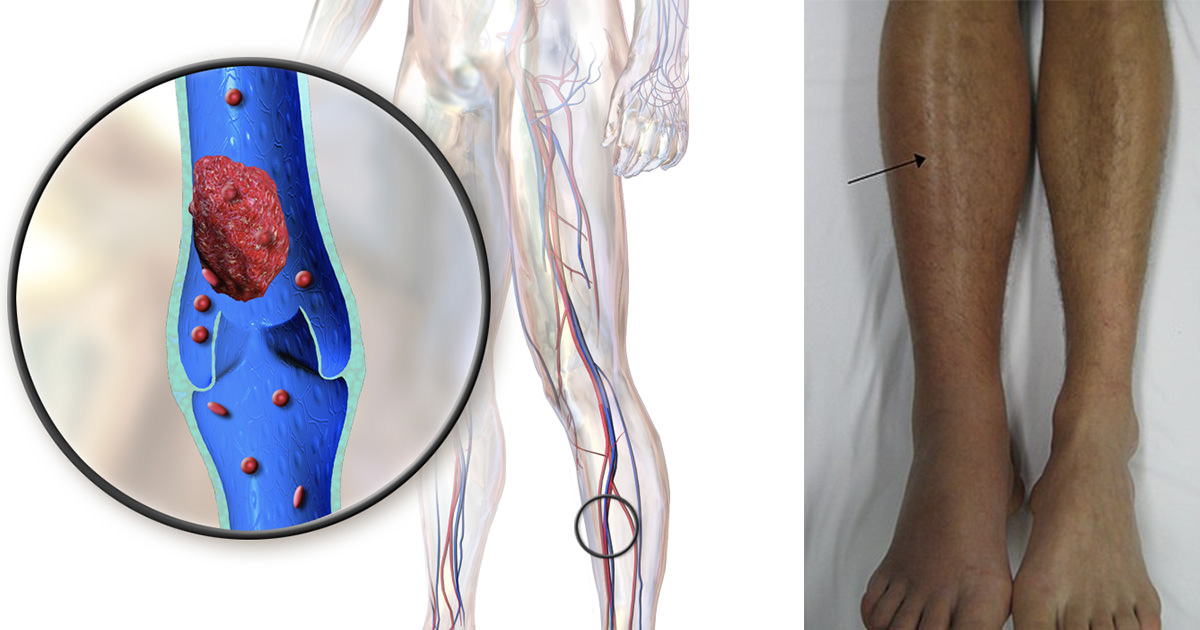

כשקריש דם נוצר בורידים העמוקים בגוף, שנמצאים בעיקר ברגליים, זה נקרא תסמונת מחלקת התיירים.

הרגליים עלולות להתנפח ולהרגיש כבדות וכלי דם חיצוניים ברגליים ייראו טוב יותר – או שאולי לא יהיו לכם תסמינים כלל.

אבל תסמונת מחלקת התיירים היא עניין רציני שיכול להוביל לתסחיף ריאתי, בו קריש דם חוסם את זרימת הדם לריאות.